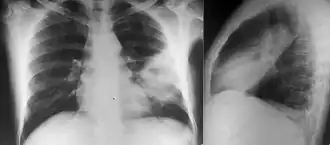

Diabetes mellitus is one of the most important risk factors in developing melioidosis. The disease should be considered in anyone who has spent time in endemic areas who develops a fever, pneumonia, or abscesses in their liver, spleen, prostate, or parotid gland.[1] The clinical manifestation of the disease can range from simple skin changes such as abscesses or ulcerations to severe organ problems.[8] The commonest organs affected are the liver, spleen, lungs, prostate, and kidneys. Among the most common features are bacteremia (in 40 to 60% of cases), pneumonia (50%), and septic shock (20%).[1][9] People with only pneumonia may have a prominent cough with sputum and shortness of breath. However, those with septic shock together with pneumonia may have minimal coughing.[2] Results of a chest X-ray can range from diffuse nodular infiltrates in those with septic shock to progressive consolidation located most commonly in the upper lobes for those with pneumonia only. Pleural effusion and empyema are more common for melioidosis affecting the lower lobes of the lungs.[2] In 10% of cases, people develop secondary pneumonia caused by other bacteria after the primary infection.[3] In northern Australia, 60% of the infected children presented with only skin lesions, while 20% presented with pneumonia.[3]

Various imaging modalities can also help with the diagnosis of melioidosis. In acute melioidosis with the spreading of the bacteria through the bloodstream, the chest X-ray shows multifocal nodular lesions. It may also show merging nodules or cavitations. For those with acute melioidosis without the spread to the bloodstream, chest X-ray most commonly shows upper lobe consolidation or cavitations.[10] In chronic melioidosis, the slow progression of upper lobe consolidation of the lungs resembles tuberculosis.[10] For abscesses located in other parts of the body apart from the lungs, especially in the liver and spleen, CT scan has higher sensitivity when compared with an ultrasound scan. In liver and splenic abscesses, an ultrasound scan shows "target-like" lesions while a CT scan shows "honeycomb sign" (abscess with loculations separated by thin septa) in liver abscesses.[10] For melioidosis involving the brain, MRI has higher sensitivity than a CT scan in diagnosing the lesion. MRI shows ring-enhancing lesions for brain melioidosis.[10]